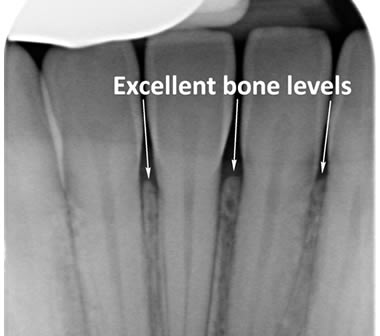

The diagrams below show the different stages of gum disease

Gingivitis is basically inflammation of the gums and is the early stage of gum disease. In gingivitis the gums become red, swollen and bleed easily. Fortunately gingivitis is completely reversible and good oral hygiene combined with thorough professional tooth cleaning can eliminate the problem.

Periodontitis is a more advanced stage of gum disease where there has been damage to the bone which supports the teeth. If left untreated periodontitis leads to more and more bone loss until the teeth start to become loose and eventually fall out by themselves or need to be extracted by a Dentist.